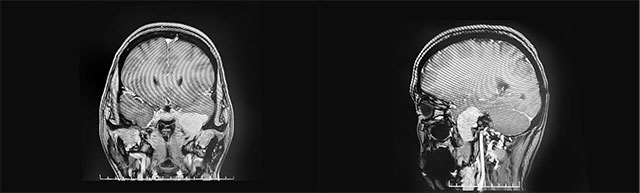

▲ 腫瘤位于左側顱中窩顳葉內(nèi)側底部

頭顱MRI平掃+增強顯示:左側顱中窩顳葉內(nèi)側底部見一腫塊影,矢橫高徑約3*4*3cm,邊緣尚清晰,形態(tài)不規(guī)則(局部向左側橋小腦角略凸起),毗鄰左側顳葉、橋腦腦組織受壓內(nèi)移,增強掃描顯著明顯強化(向左側橋小腦角凸起灶環(huán)狀強化)。

結合患者病情和影像學檢查,潘仁龍主任、李士其教授、吳治群博士會診后指出,考慮為神經(jīng)纖維瘤。正是腫瘤壓迫三叉神經(jīng)導致其面部麻木疼痛,患者手術指征明確,應盡快手術。